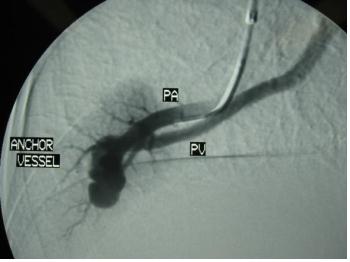

末端动脉阻塞(end-artery occlusion)

末端动脉栓塞:医源性肾损伤-移植肾活检

活检后动脉瘤破裂 |

微导管在载瘤动脉末端 |

载瘤动脉末端栓塞 |

Coil=3 |